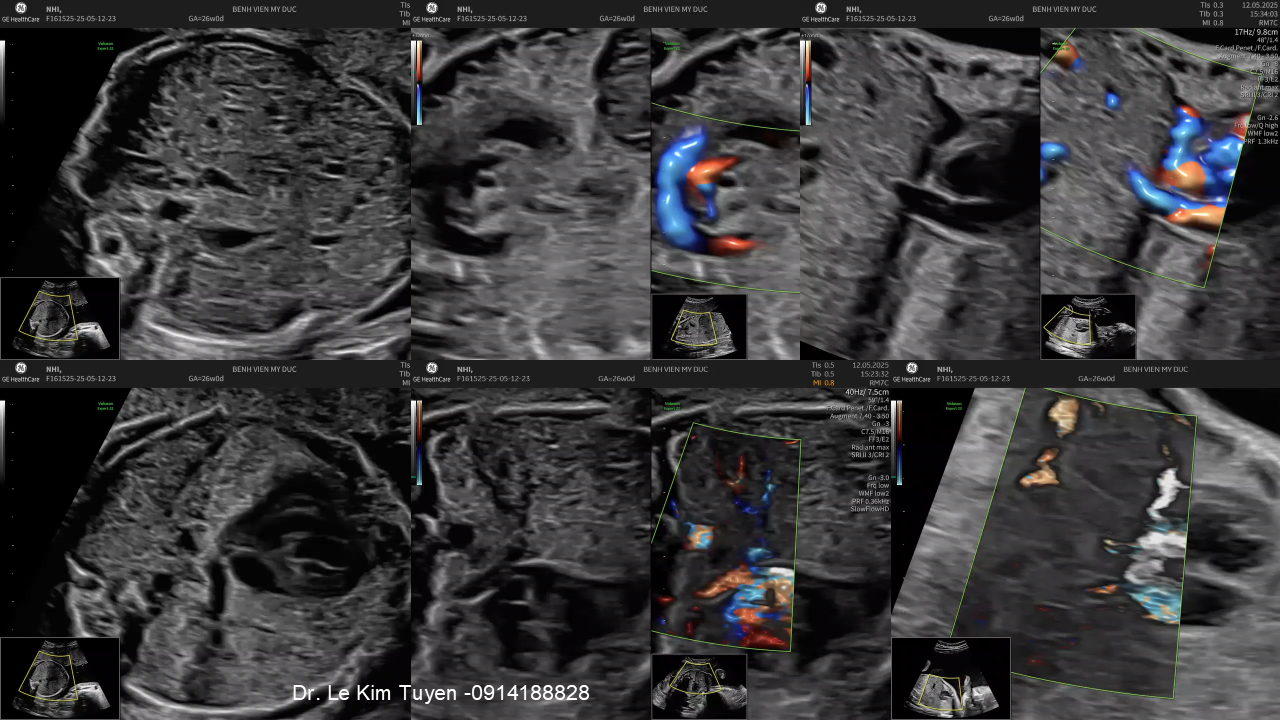

Áp dụng công nghệ Graphicflow trong phát hiện bệnh tim bẩm sinh cần cấp cứu sơ sinh

TS. BS. Lê Kim Tuyến